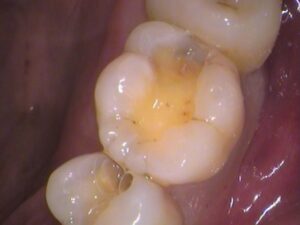

セラミックがセットされました

後日、出来上がったセラミックを装着します。

治療した箇所が分からないくらい綺麗に仕上がりました(^^)/

セラミックが入っていますが、色や形を歯に合わせているので、どこを治療したのか分かりませんね!